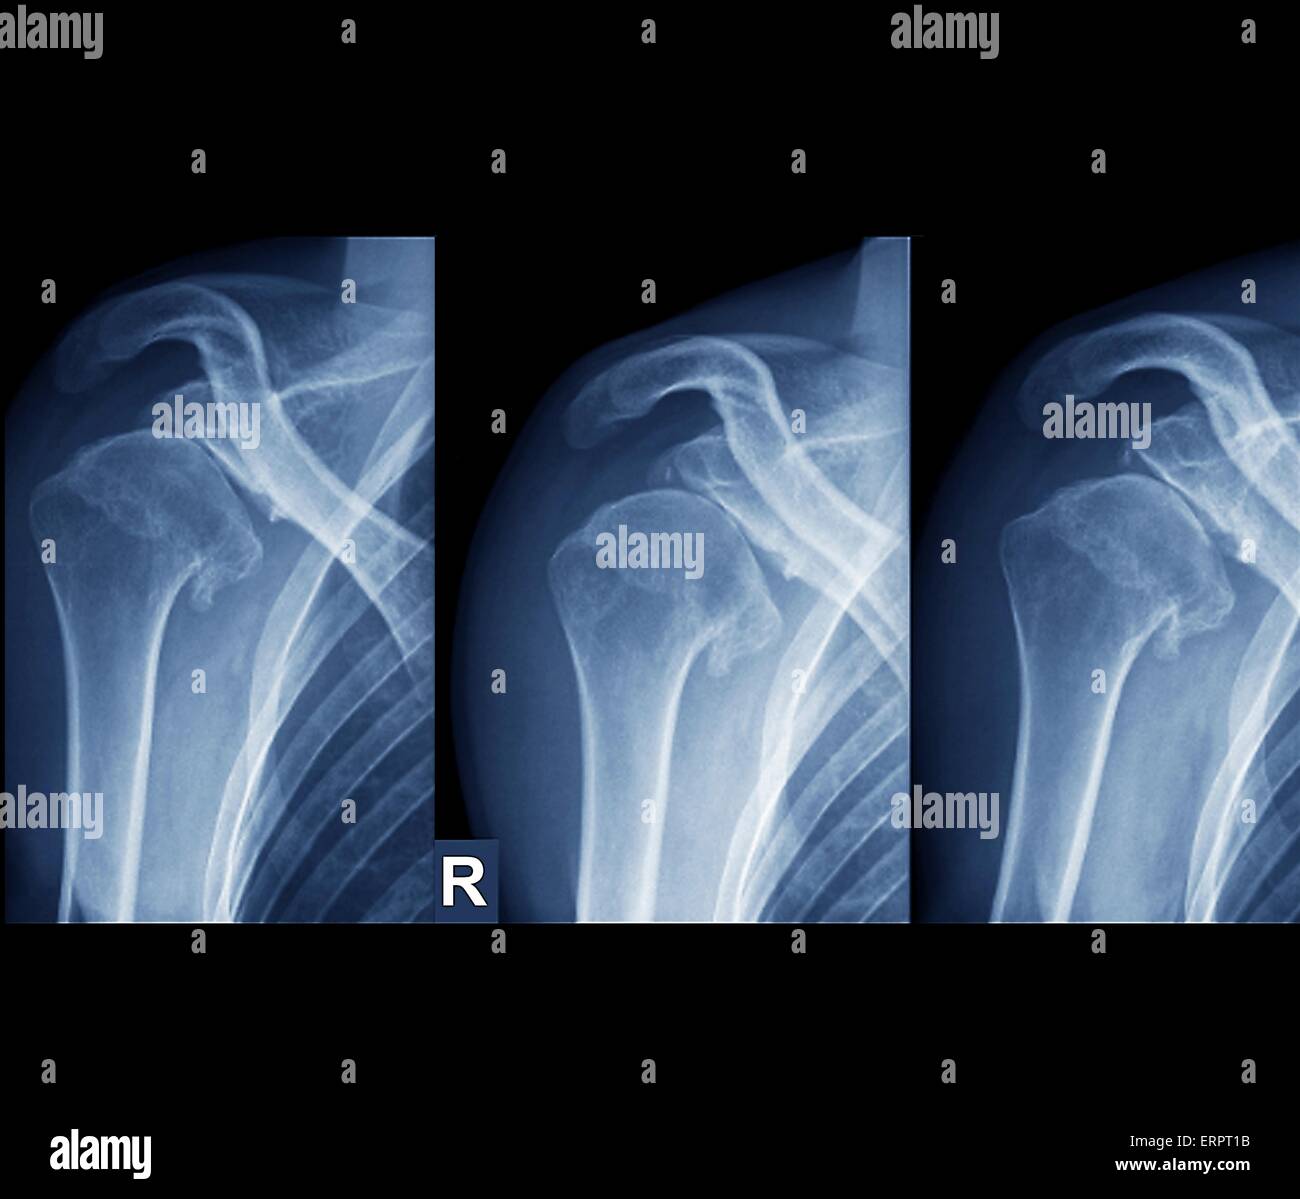

X Ray Shoulder Internal Rotation . Diagram of internal rotation of the shoulder. The stronger the magnet, the higher the intrinsic. The red arrow points to the lesser tubercle of the humerus in profile. Ap in internal rotation for visualization of the lesser tuberosity. The red shaded oval is the overlap between the humeral head and. The humeral head will lie posterior to the glenoid fossa. Mri is best for evaluating soft tissue structures and evaluating bone contusions or trabelcular microfractures. Radiographic examination of shoulder in ap view with internal rotation. The glenohumeral joint will be widened and the humeral head will take on a classic “light bulb” appearance due to forced internal rotation of the humerus. The american college of radiology recommends at least 3 views for acute traumatic shoulder pain [5]: Radiographic positioning included in this video are the anteroposterior (ap) internal rotation and. This projection demonstrate fracture and dislocation of the proximal humerus and shoulder girdle. The shoulder series is fundamentally composed of two orthogonal views of the glenohumeral joint including the entire.

X Ray Shoulder Internal Rotation The red shaded oval is the overlap between the humeral head and. The shoulder series is fundamentally composed of two orthogonal views of the glenohumeral joint including the entire. Mri is best for evaluating soft tissue structures and evaluating bone contusions or trabelcular microfractures. Diagram of internal rotation of the shoulder. The stronger the magnet, the higher the intrinsic. The american college of radiology recommends at least 3 views for acute traumatic shoulder pain [5]: Radiographic examination of shoulder in ap view with internal rotation. The red arrow points to the lesser tubercle of the humerus in profile. Radiographic positioning included in this video are the anteroposterior (ap) internal rotation and. The red shaded oval is the overlap between the humeral head and. The humeral head will lie posterior to the glenoid fossa. Ap in internal rotation for visualization of the lesser tuberosity. The glenohumeral joint will be widened and the humeral head will take on a classic “light bulb” appearance due to forced internal rotation of the humerus. This projection demonstrate fracture and dislocation of the proximal humerus and shoulder girdle.

SHOULDER GIRDLE Radiology Key X Ray Shoulder Internal Rotation The american college of radiology recommends at least 3 views for acute traumatic shoulder pain [5]: Mri is best for evaluating soft tissue structures and evaluating bone contusions or trabelcular microfractures. Radiographic examination of shoulder in ap view with internal rotation. This projection demonstrate fracture and dislocation of the proximal humerus and shoulder girdle. Diagram of internal rotation of the. X Ray Shoulder Internal Rotation.